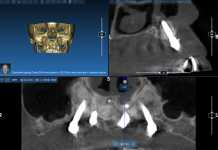

Un esame completo dei tessuti duri e molli veniva realizzato per ogni singolo paziente. Le ortopantomografie rappresentavano la base per lo studio preliminare, che veniva completato, ove necessario, da una moderna tomografia assiale computerizzata di tipo volumetrico (i-CatR, Imaging Sciences International, Hartfield, PA, USA). I dati derivanti dalla TAC volumetrica erano trasferiti immediatamente a uno specifico software di navigazione implantare (SimplantR, Materialise, Leuven, Belgium), allo scopo di realizzare una ricostruzione tridimensionale delle ossa mascellari. Con l’ausilio di questo software, era possibile determinare precisamente l’altezza, lo spessore e l’angolazione della cresta ossea in corrispondenza di ciascun sito implantare, insieme con la densità della corticale e della midollare; veniva quindi simulato l’inserimento dell’impianto. Qualora necessario, inoltre, sulla base di queste informazioni, veniva realizzata una dima chirurgica stereolitografica (SurgiguideR, Materialise, Leuven, Belgium) per il corretto posizionamento degli impianti, «guidato» dal progetto tridimensionale precedentemente elaborato. Lo studio preliminare includeva naturalmente un esame dei modelli e un’accurata ceratura diagnostica.